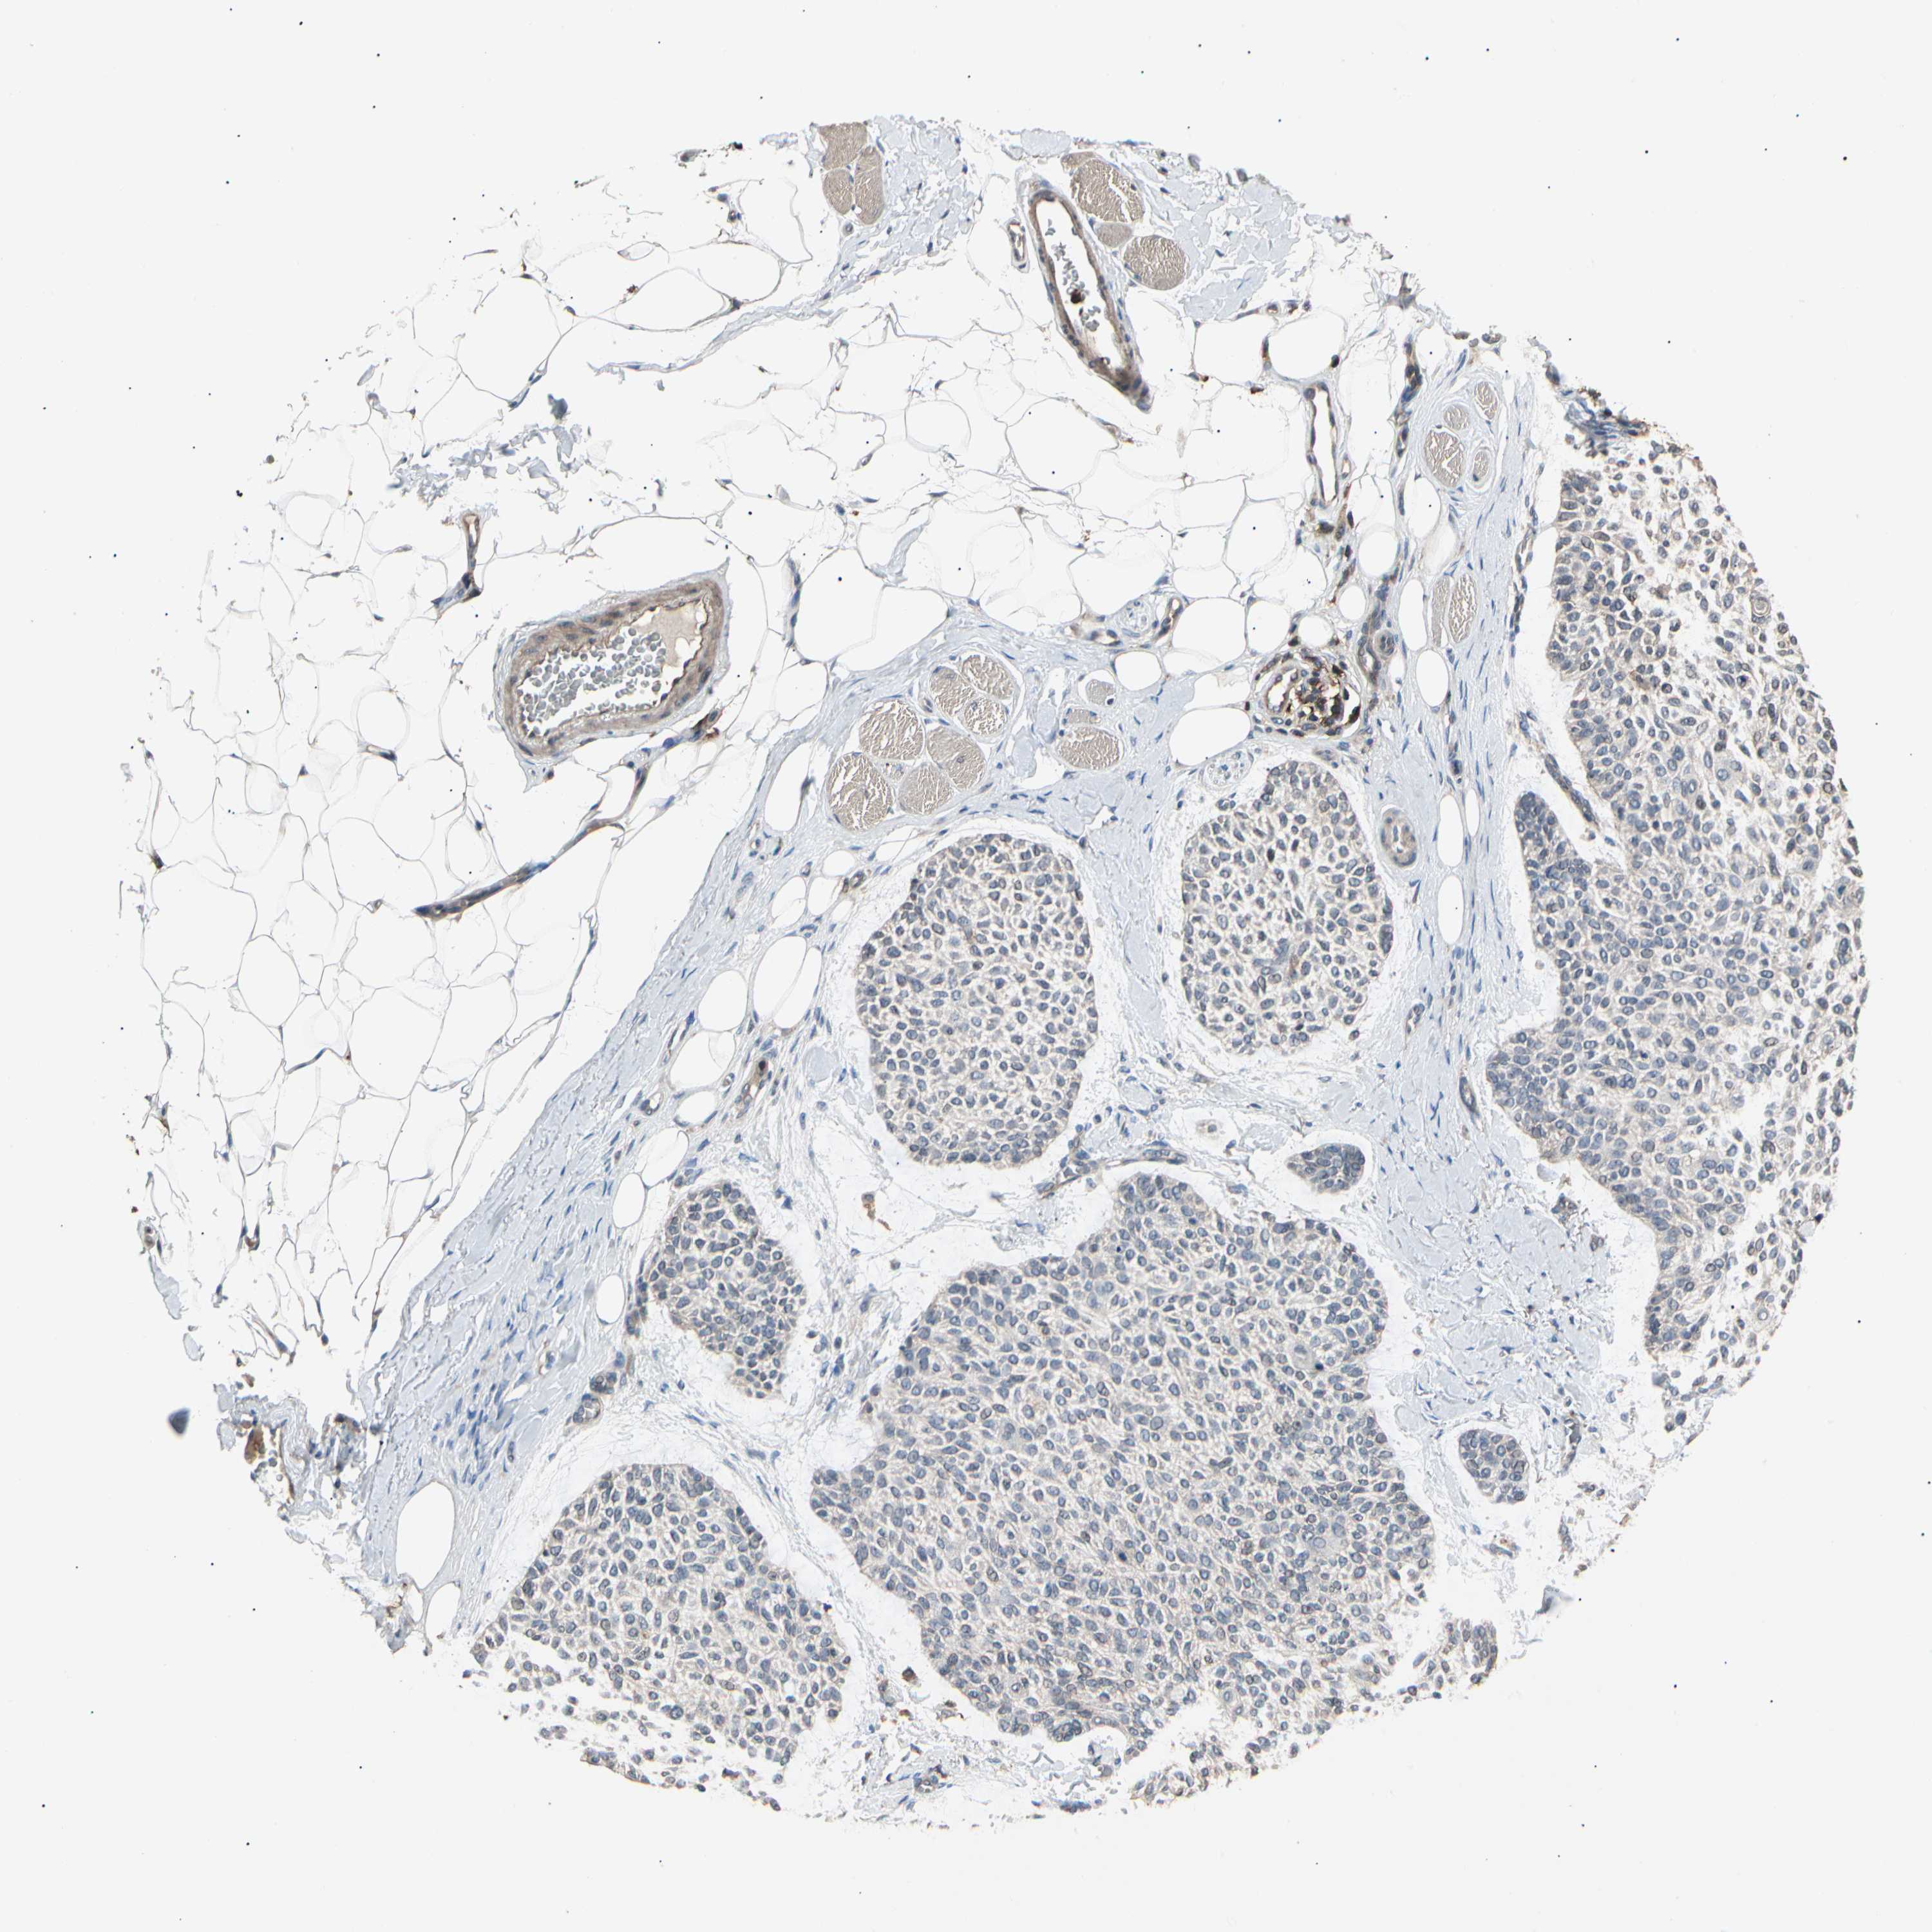

SKIN CANCER - Protein expressioni

A mouse-over function shows sample information and annotation data. Click on an image to view it in a full screen mode. Samples can be filtered based on level of antibody staining by selecting one or several of the following categories: high, medium, low and not detected. The assay and annotation is described here.

Antibody stainingi

Antibody staining in the annotated cell types in the current human tissue is reported as not detected, low, medium, or high, based on conventional immunohistochemistry profiling in selected tissues. This score is based on the combination of the staining intensity and fraction of stained cells.

Each image is clickable and will lead to virtual microscopy that enables deeper exploration of all samples and also displays staining intensity scores, fraction scores and subcellular localization as well as patient and tissue information for each sample.

Antibody CAB025854

Staining

High

Medium

Low

Not detected

Intensity

Strong

Moderate

Weak

Negative

Quantity

>75%

75%-25%

<25%

None

Location

Nuclear

Cytoplasmic/membranous

Cytoplasmic/membranous,nuclear

Basal cell carcinoma

Squamous cell carcinoma, NOS

Squamous cell carcinoma, metastatic, NOS